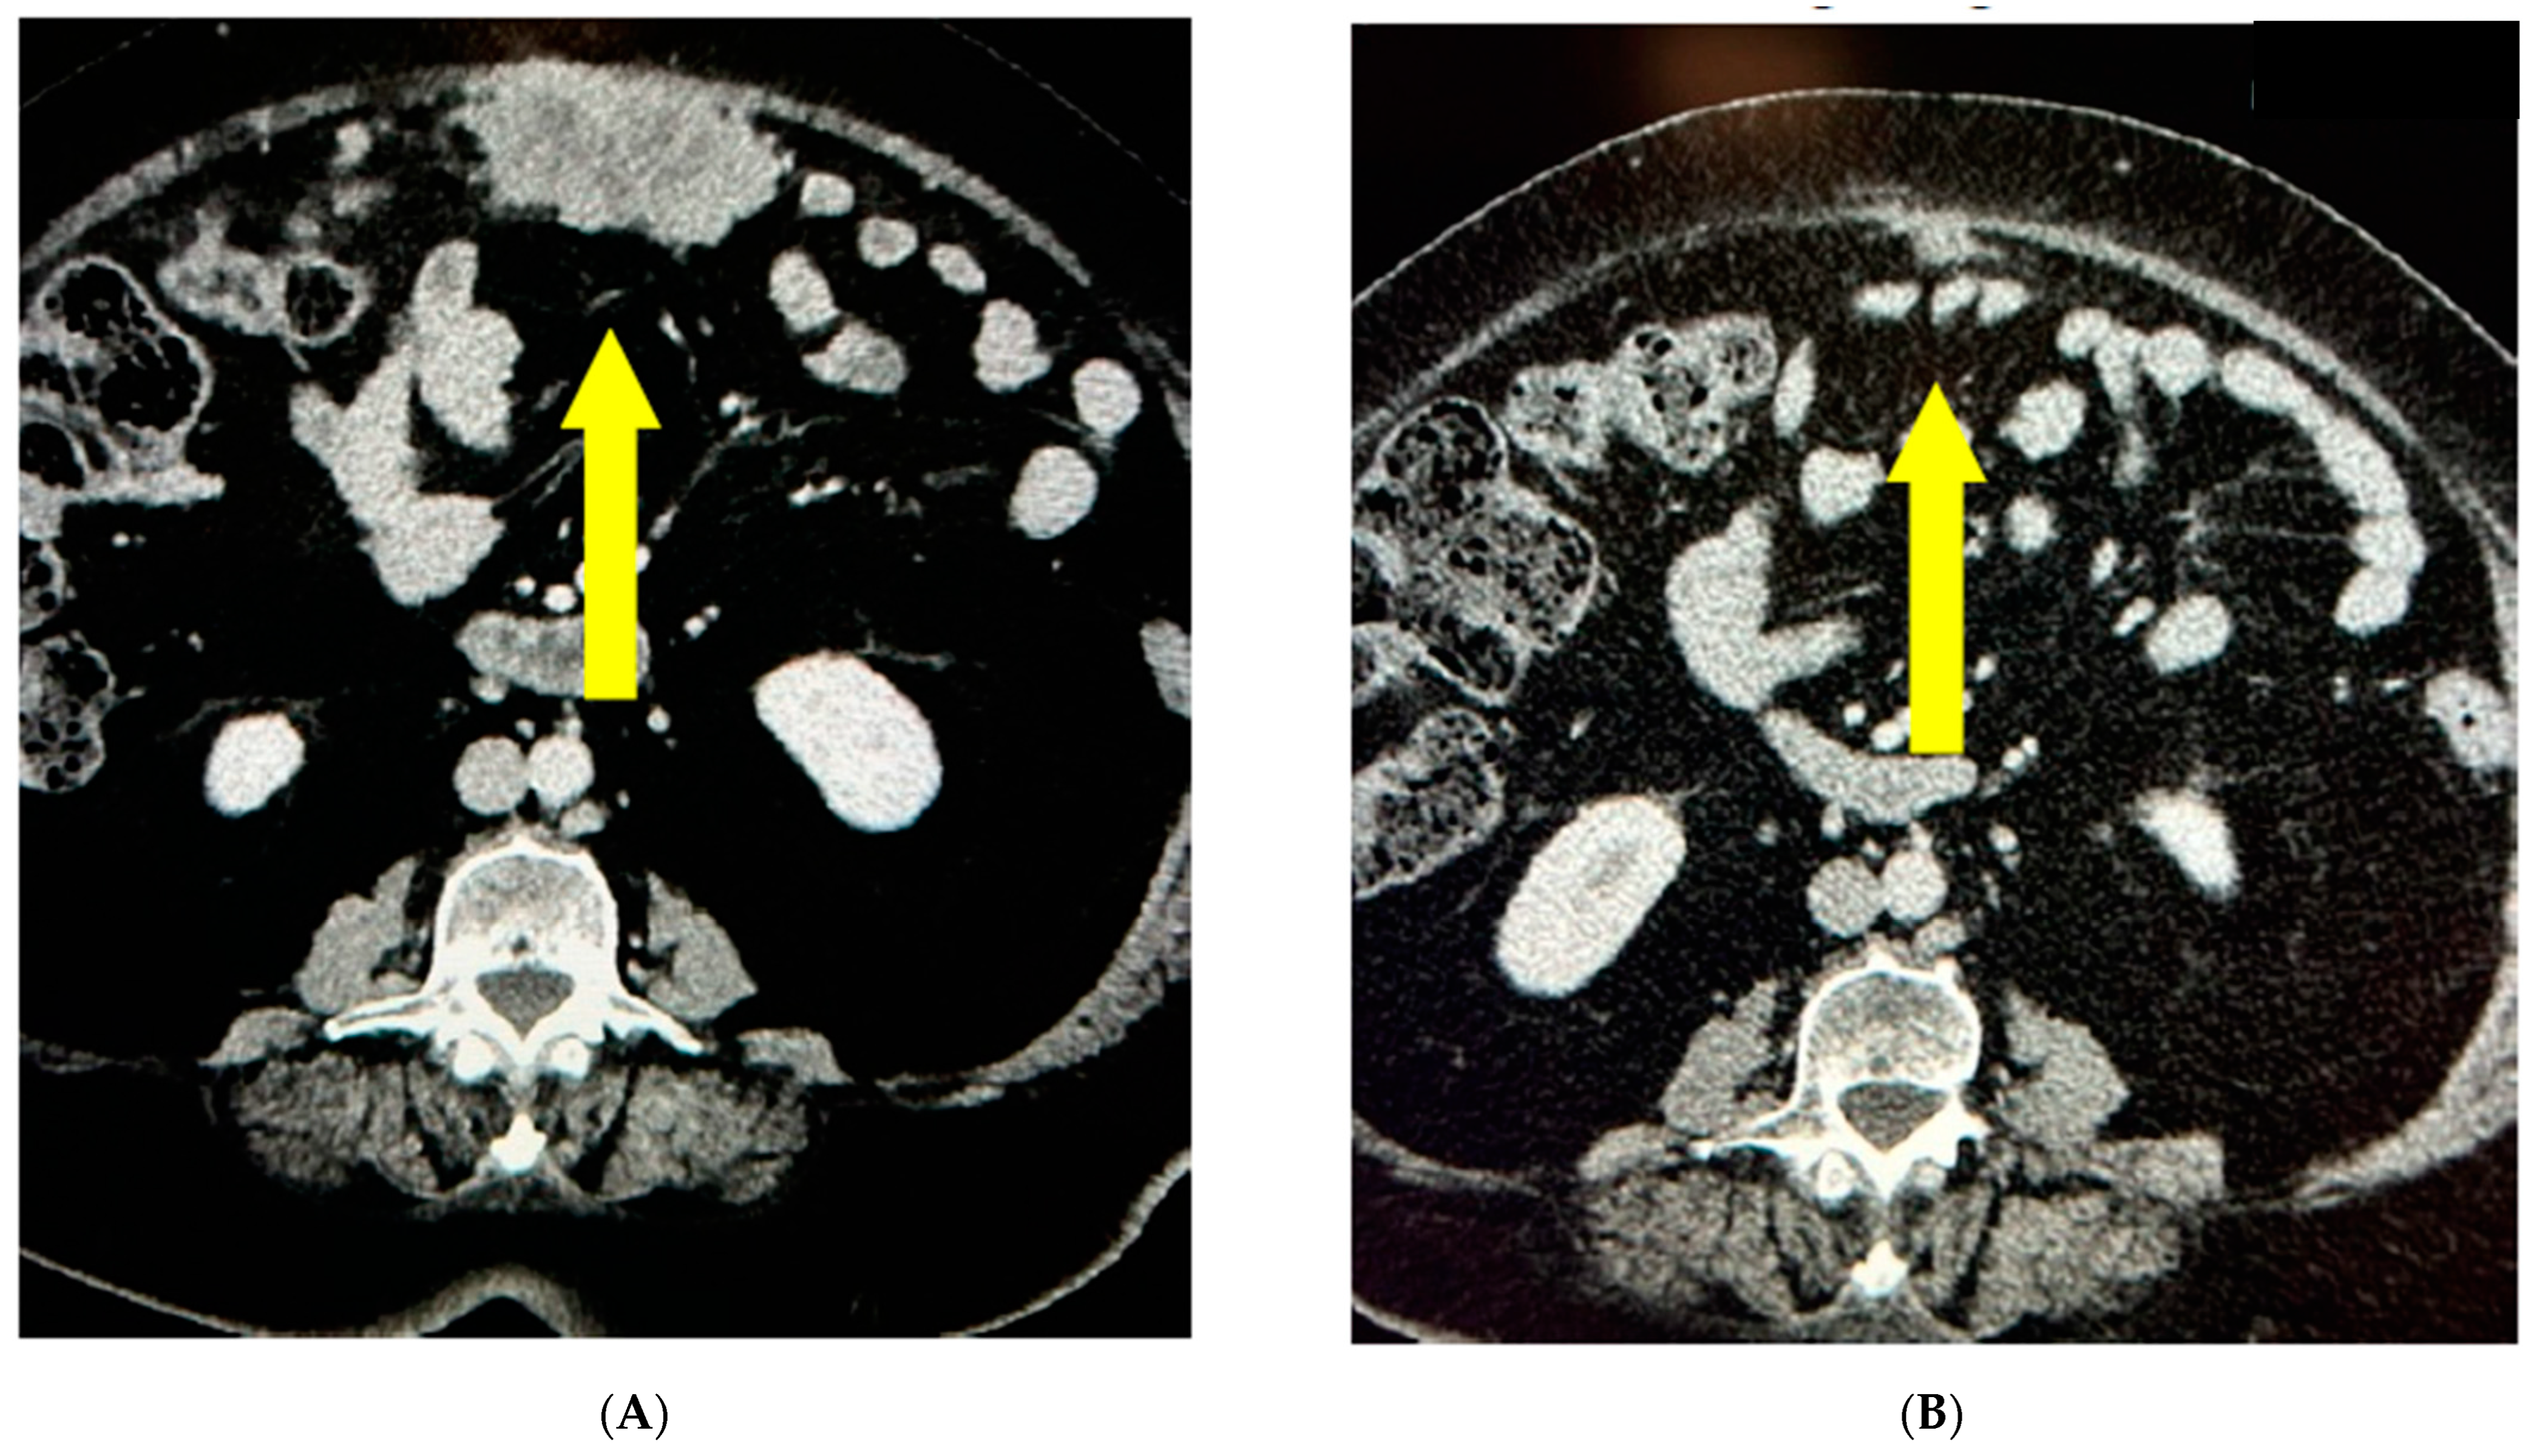

- Case 1:

- Case 2:

- Case 3:

- Case 4:

- Case 5:

- Case 6: